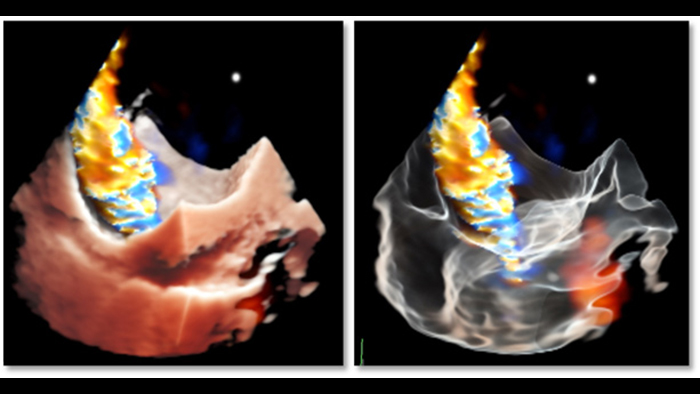

Deep insights with TrueVue color and GlassVue

Cardiac TrueVue photorealistic rendering with MultiVue image alignment

ASD closure with EchoNavigator live fusion